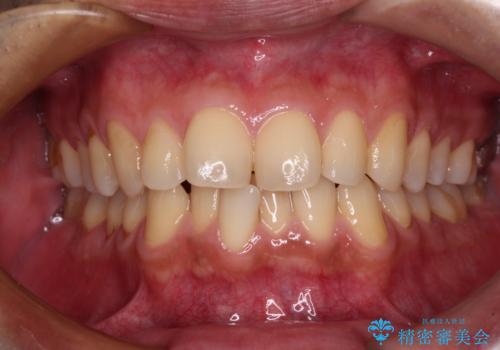

[ マウスピース矯正治療 ] がたつき ねじれのある前歯をきれいにしたい

![[ マウスピース矯正治療 ] がたつき ねじれのある前歯をきれいにしたいの症例 治療前](https://seimitsushinbi.jp/wp/wp-content/uploads/2025/04/8438e7299f1b9566ac213e8e9f7db5f6-500x350.jpg?v=1745226068)

![[ マウスピース矯正治療 ] がたつき ねじれのある前歯をきれいにしたいの症例 治療後](https://seimitsushinbi.jp/wp/wp-content/uploads/2025/04/IMG_0097-500x350.jpg?v=1745225947)